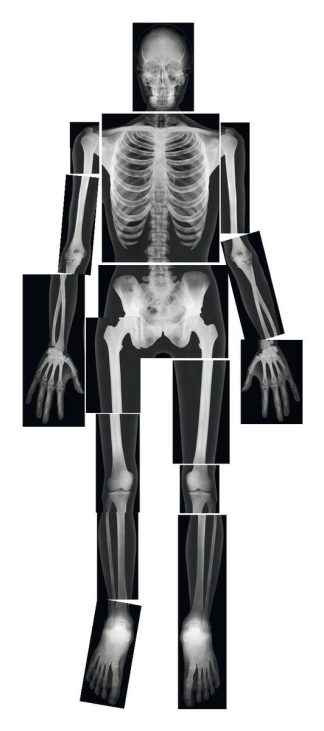

Innehåller 10 bilder som vid vinkling ändras och visar vad som händer i våra största organ i kroppen.

Innehåller bl.a. Hjärtat, Lungorna och hjärnan mm.